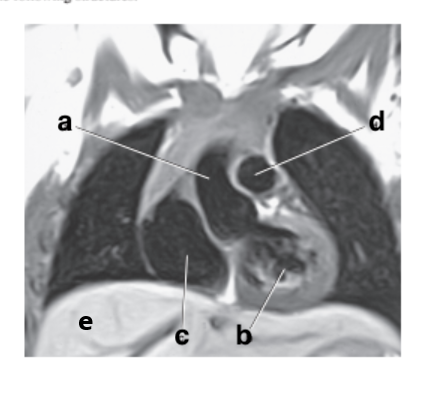

What is letter b?

Left ventricle

What is letter c?

Aortic arch

What is letter a?

Vertebral artery

Ascending aorta

What is letter e?

Descending aorta

Interventricular septum